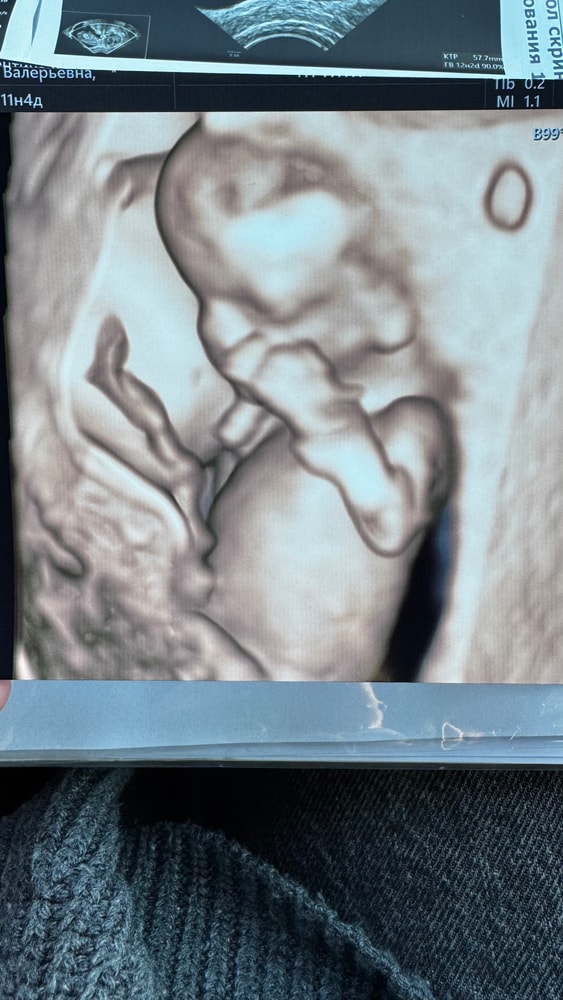

Первый скрининг

И вот вчера был первый скрининг! С малышом все хорошо, курносик такой 😍 45 минут мы его с мужем разглядывали – это невероятно! КТР уже почти 6 см, все риски низкие, прикрепился по передней стенке. Брыкался-пинался на узи 😁 Опережает акушерский срок на 5 дней.